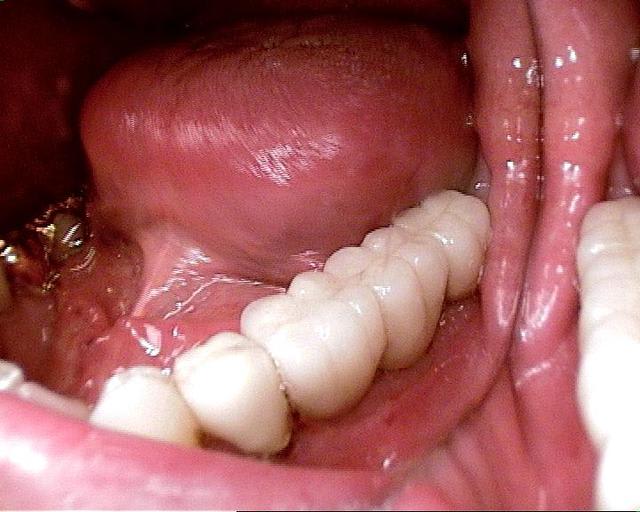

Pour ceux que ca interessent, et parce qu on a m a demandé des cas supplémentaires dans le sujet 23 implants rehabilitation totale, voici un autre cas d implantation immédiate avec la technique minimalement invasive et condensation grace aux forets.

Le patient a reçu un traitement il y a dix ans dans le maxillaire et dans le 4eme quadrant.Comme on peut le voir j´ai du extraire quelques dents au maxillaire: 35 37 et 45.

Le septum de la 37 a été foré avec un foret conique 3 faces.

J ai planté à 60 Ncm sans fracturer le septum.Juste après l opération , les prep caps en zircon ont été cémenté.La restauration définitive 34 jusqu` à 37 été fixé 2 semaines après l implantation avec implantlink (detax). Après un an, le bridge a été retiré facilement pour voir l´état de la gencive et faire une radio de contrôle.On la re ossifiction est satisfaisante et que la gencive "aime" le zircon.

Le bridge a ensuite été recémenté sans correction nécessaire du bridge.